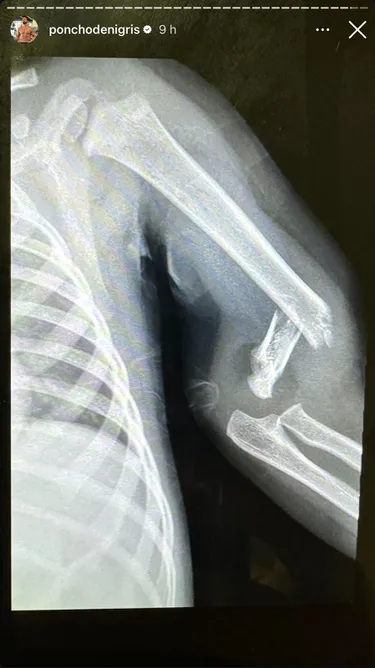

Poncho también compartió una imagen de la radiografía del brazo de su hijo, en el que se aprecia claramente la fractura.

Monterrey, Nuevo León - El hijo menor del influencer Poncho De Nigris, conocido como Toñito, sufrió un accidente mientras jugaba con sus hermanos y se rompió un brazo, según reveló la estrella del reality 'La Casa de los Famosos México'.

"Tuvimos un accidente leve, lo que pasa con los niños, pero que nunca nos había pasado… se quebró un bracito Toño por andar jugando en la calle, se me hace que error mío, se me hace”, afirma Poncho en el video en el que compartió la noticia.

“No es nada grave, pero está feo, se siente bien feo… se siente horrible que por tu culpa, por nada, se quiebre el brazo uno de tus hijos”, afirmó.